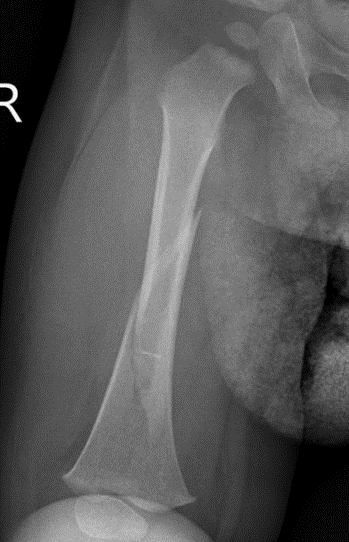

Flexible nails / Titantium Elastic Nails

Indications

Length stable fractures i.e simple transverse, short oblique

Midshaft fractures

Maximum weight up to 50 kg / 12 years old

Flexible nail technique

Wires

- available 1. 5 mm - 4.0 mm

- 30 - 40% of diameter of diaphyseal medullary canal

- i.e. if canal 10 mm wide, use 2 x 4 mm

- recommend using 2 wires same diameter to avoid rotational instability

Entry points

- medial and lateral insertion

- 1 - 2 cm proximal to distal femoral physis

- oblique entry with awl in direction of nail insertion

- can open with drill bit

- beware proximity of the femoral artery medially

- entry points should be symmetrical

Wire passage

- bend wire for 3 point fixation with bend at fracture site

- also bend the tip of the wire

- can use F Tool to reduce fracture / sheet in groin

- may need small incision and open reduction

- medial entry wire will pass into femoral neck

- lateral wire will pass into greater trochanter / medial wire into femoral neck

- use designated TEN wire cutter to cut wires

- cut off, tap in slightly further, leave 1.5 cm out so can retrieve

- wires that are too prominent can cause bursa / limit flexion / pain / protrude through skin

Acceptable alignment

- 10o varus / valgus

- 15o flexion / extension

- 15 mm shortening